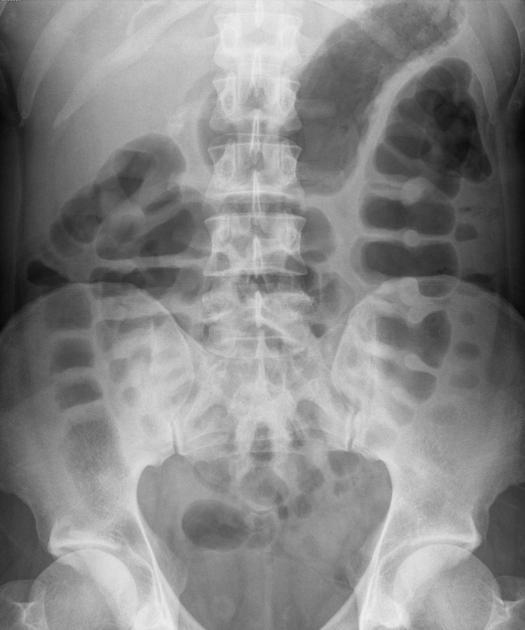

est exceptionnelle . Image radiologique de la cliche de face

ASP thoraco-abdominale est aspect de image de

distendue du colon occlusive bas , image hydroaerique de

type colique et espace de vacuitee pelvienne . Image

Cliche ASP de face et de profile : Image radiologique

le plus souvent est image de dilatation distendue du colon

avec image de vacuite pelvienne . Dans cas de fistule de

voie urinaire on peut se retrouve de image de la presence de

l'air dans la vessie et tache de calcifie de meconium dans le

colon .

Image radiologique ASP de

face d'une imperfoaration anale cher une nourrison

avec aspect de dilatation gazeuse tres distendue du

colon transverse et colon descendant et de ileon .

Le foie et deux coupole diaprgahmatique sont tres

elevees . Cliche de face ASP , decubitus dorsale |